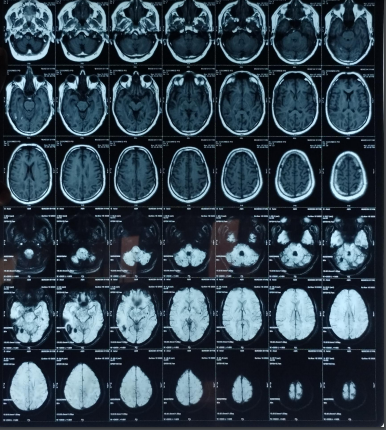

The patient’s routine blood investigations were normal. Serology for HIV, hepatitis B, C, and syphilis was negative. His MRI brain showed a parenchymal bleed in right temporo occipital regions with intra-ventricular leakage of blood and tiny petechial haemorrhage in brain parenchyma bilateral. extensive signal changes in cerebellar hemisphere, bilateral gangliothalamocapsular region, pons, midbrain and deep white matter of both cerebral hemisphere? Microangiopathy? CADASIL.

Early-onset dementia (onset before age 65) is a thought-provoking ailment with many possible causes, including early-onset familial Alzheimer’s disease, frontotemporal lobar degeneration, Parkinson’s dementia, Lewy body dementia, disorders of amino acid and organic acid metabolism, leukodystrophies, lysosomal storage diseases, disorders of metal metabolism, and mitochondrial diseases [6]. In our patient, the history, physical examination, laboratory investigations, and neuroimaging were not suggestive of these causes and prompted the search for a rare etiology. The most common MRI finding associated with CADASIL is basal ganglia and white matter hyperintensities in T2-weighted sequences that start as punctate or nodular foci and then often become confluent, extensive, and usually symmetrical, mainly in the periventricular region, anterior temporal pole, external capsule, the centrum semiovale, and frontal and parietal areas. In our patient, diagnosis was made mainly from MRI findings as seen in fig. 1, 2.

Fig. 2: Extensive hyperintensity on T2W/FLAIR sequence is seen in bilateral thalamus and basal ganglia, both cerebellar hemisphere, mid brain, pons and in deep white matter of both cerebral hemispheres